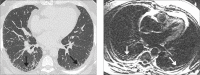

Methods: Twenty patients with idiopathic pulmonary fibrosis (IPF) and twelve control patients underwent late-enhanced MRI and high-resolution CT. Tissue characterization of PF was depicted using a segmented inversion-recovery turbo low-angle shot MRI sequence. Pulmonary arterial blood pool nulling was achieved by nulling main pulmonary artery signal. Images were read in random order by a blinded reader for presence and extent of overall PF (reticulation and honeycombing) at five anatomic levels. Overall extent of IPF was estimated to the nearest 5% as well as an evaluation of the ratios of IPF made up of reticulation and honeycombing. Overall grade of severity was dependent on the extent of reticulation and honeycombing.

Results: No control patient exhibited contrast enhancement on lung late-enhanced MRI. All IPF patients were identified with late-enhanced MRI. Mean signal intensity of the late-enhanced fibrotic lung was 31.8±10.6 vs. 10.5±1.6 for normal lung regions, P < 0.001, resulting in a percent elevation in signal intensity from PF of 204.8%±90.6 compared with the signal intensity of normal lung. The mean contrast-to-noise ratio was 22.8±10.7. Late-enhanced MRI correlated significantly with chest CT for the extent of PF (R=0.78, P = 0.001) but not for reticulation, honeycombing, or coarseness of reticulation or honeycombing.

Conclusion: Tissue characterization of IPF is possible using inversion recovery sequence thoracic MRI.